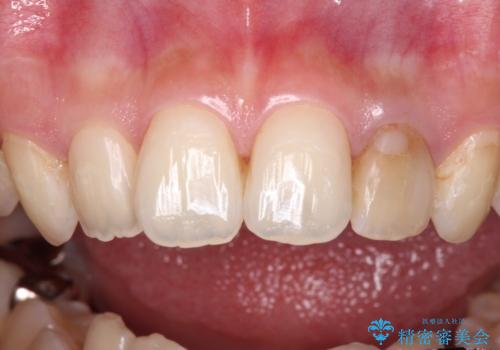

- 根管治療後に10年以上経過し、変色した前歯を気にして来院された患者様です。

根管治療はやり直さずに、ファイバーポストを使用した土台を植立してオールセラミッククラウンにて補綴することとしました。